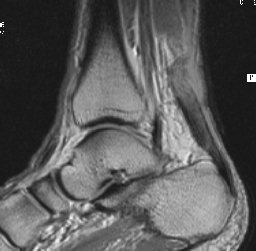

12251.jpg (12881 bytes) 12287.jpg (14606 bytes)

History

Description

Diagnosis